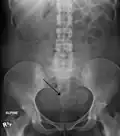

Diagnostic methodPelvic examination, medical imaging[1]

Physical examination and ultrasound are sufficient for diagnosing uterine fibroids in the majority of people. When ultrasound findings are inconclusive, magnetic resonance imaging (MRI) may be able to confirm the diagnosis of uterine fibroids in most cases. In addition, MRI can identify benign uterine fibroids with atypical imaging features and fibroids with variant growth patterns. MRI can also identify other uterine (e.g. adenomyosis, endometrial polyps, endometrial cancer) and extrauterine (e.g. benign and malignant ovarian tumors, endometriosis) disorders that may mimic the appearance of uterine fibroids and/or contribute to the patient's symptoms.[38] However, a small proportion of uterine fibroids can mimic other malignant uterine tumors (e.g. leiomyosarcoma) on all available imaging modalities (e.g. ultrasound, CT, MRI and PET-CT).[38]